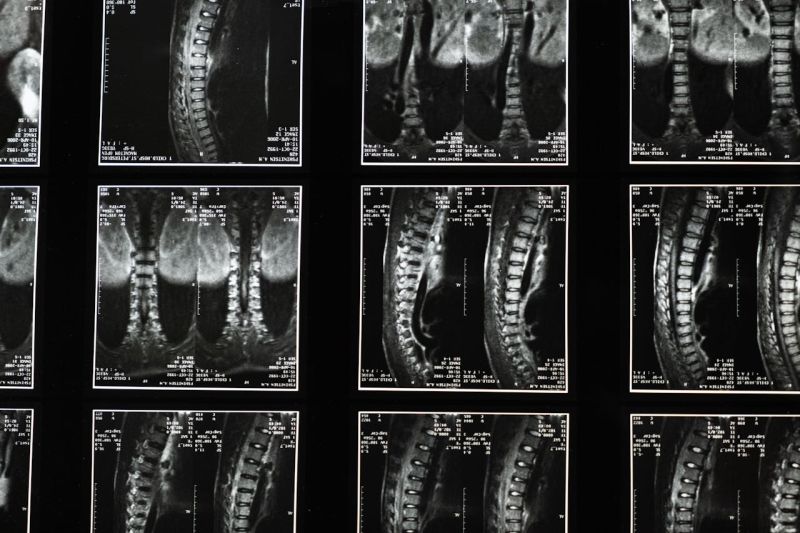

Šta magnetna rezonanca kičme može da otkrije?

Ovaj pregled daje lekarima detaljan uvid u strukturu kičme i promene na njoj. Magnetna rezonanca je trenutno najosetljivija metoda za pregled kičmenog stuba, i može da prikaže:

• Anatomiju kičmenog stuba i pravilnost njegovog poravnanja. Jasno se vizualizuju svi pršljenovi, međupršljenski diskovi, kičmena moždina, živci i okolna meka tkiva (mišići i ligamenti).

• Promene na međupršljenskim diskovima: degenerativne procese (istrošenost diska, gubitak elastičnosti i visine), kao i hernije diska - kada deo diska ispada iz svog ležišta i pritiska okolne nerve.

• Suženje kičmenog kanala (spinalna stenoza) zbog izraslina na kostima ili ispupčenja diskova, što može dovesti do pritiska na kičmenu moždinu ili živčane korenove.

Zahvaljujući izuzetnoj rezoluciji slike, magnetna rezonanca često otkrije i suptilne promene u tkivima koje druge metode (poput klasičnog snimanja ili skenera) ne mogu uočiti. To pomaže lekaru da postavi preciznu dijagnozu i odredi optimalan plan lečenja.